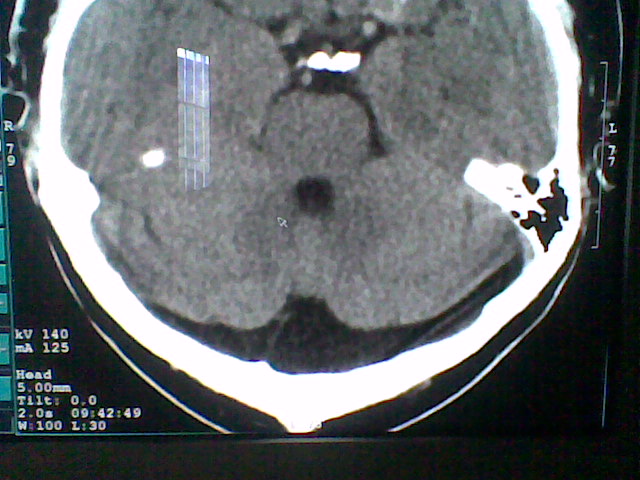

标题: CT21502:这个正常的么?

患者,男,头晕4天来诊,要求ct。

大枕大池合并蛛网膜囊肿。

支持 大枕大池合并蛛网膜囊肿。

考虑大枕大池合并蛛网膜囊肿。

有没有dandy-walker综合征的可能?